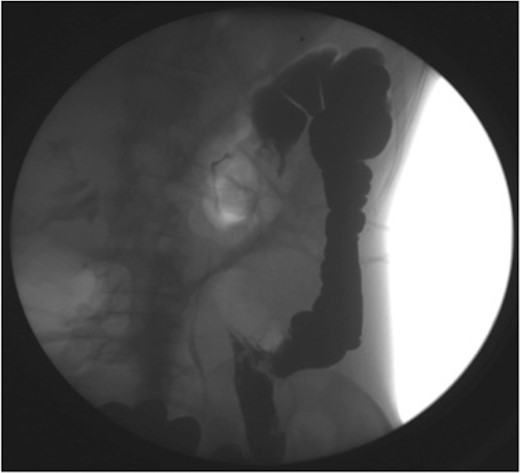

A gastrografin enema (Fig. 4) failed to demonstrate any flow beyond the mid-transverse colon. A presumptive diagnosis of transverse colon obstruction was made and the patient was taken to theatre.

Gastrografin enema (Case 2) demonstrating no flow beyond the mid-transverse colon.